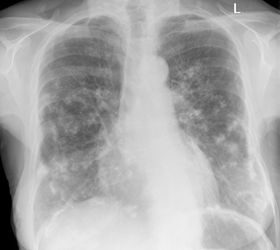

Ein Lungenödem ist eine Ansammlung von Flüssigkeit im Lungengewebe die unter gesunden Bedingungen nicht vorhanden ist. Das Ziel ist eine Balance zwischen neuem Wasser in der Lunge und Entwässerung durch Medikamente zu finden. Teile der Atemwege sind blockiert und es kommt zu Atemnot.

Hier bilden sich zwischen Lunge und Rippenfell Wassereinlagerungen die die Lunge zusammendrücken und so die Atemnot entsteht. Nach der Beschreibung des Krankheitsbildes handelt es sich nicht um Wasser in der Lunge Lungenödem sondernum einen Pleura- Erguss. Das Lungenödem auch Wasserlunge und pulmonales Ödem genannt beschreibt eine Flüssigkeitsansammlung in der Lunge.

Beitrag 2 Grundsätzlich sind meist Herz-und Nierenerkrankungen Auslöser für ein Lungenödem. Wenn die Nieren nicht mehr richtig arbeiten wird nicht mehr ausreichend Flüssigkeit aus dem Körper ausgeschieden. Teile der Atemwege sind blockiert und es kommt zu Atemnot. Auch bei FIP-Erkrankungen kommt es oft zu einer Flüssigkeitsansammlung in der Lunge allerdings betrifft FIP idR. Wasser auf der Lunge ist allermeistens durch eine Herzschwäche verursacht. Dann wiederum wird die Lunge nicht mehr ausreichend belüftet wodurch die Durchblutung und der Gasaustausch beeinträchtigt werden. Diese sind allerdings vielfältig betreffen aber letztlich alle die linke Herzkammer deren Dysfunktion zu einem Blutrückstau in der Lunge führt die Folge ist dass sich Flüssigkeit im Bereich der Lungenbläschen ansammelt die der Luft den Platz nimmt die Atmung aufrechtzuerhalten. Das Ziel ist eine Balance zwischen neuem Wasser in der Lunge und Entwässerung durch Medikamente zu finden. Das Lungenödem auch Wasserlunge und pulmonales Ödem genannt beschreibt eine Flüssigkeitsansammlung in der Lunge.